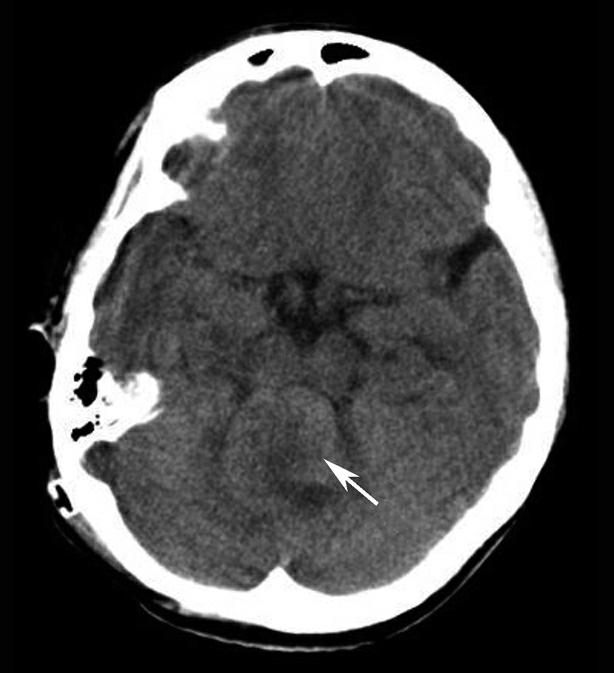

破裂孔、卵圆孔、棘孔及斜坡等均为重要的解剖结构,临床常见疾病如鼻咽癌常侵犯上述结构(图1-2-3)。颈静脉孔区较常见的肿瘤为颈静脉球瘤,常伴有颈静脉孔及其邻近骨质的破坏(图1-2-4)。

图1-2-3 鼻咽癌颅底骨质破坏

A.横断面;B.横断面(骨窗)

骨窗示左侧岩尖、斜坡、左侧蝶骨大翼骨质破坏、受侵(白箭),肿瘤经破裂孔侵入颅内(黑箭头)

图1-2-4 右侧颈静脉球瘤

A.横断面(骨窗);B.横断面

右侧颈静脉孔区不规则骨质破坏(箭),局部见软组织肿块(☆)